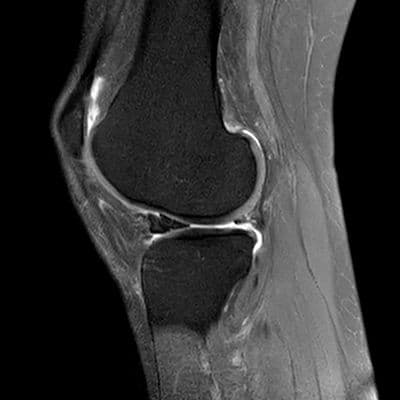

Volumineuse lésion en anse de seau du ménisque latéral avec luxation du fragment méniscal sur le profil antérieur de l'échancrure inter-condylienne, conservation de l'attache méniscale antérieure, l'attache méniscale postérieure apparaît rompu.

Le diagnostic est confirmé par IRM, qui montre des signes caractéristiques comme le "double LCP" ou l'absence de "nœud papillon" sur les coupes sagittales.